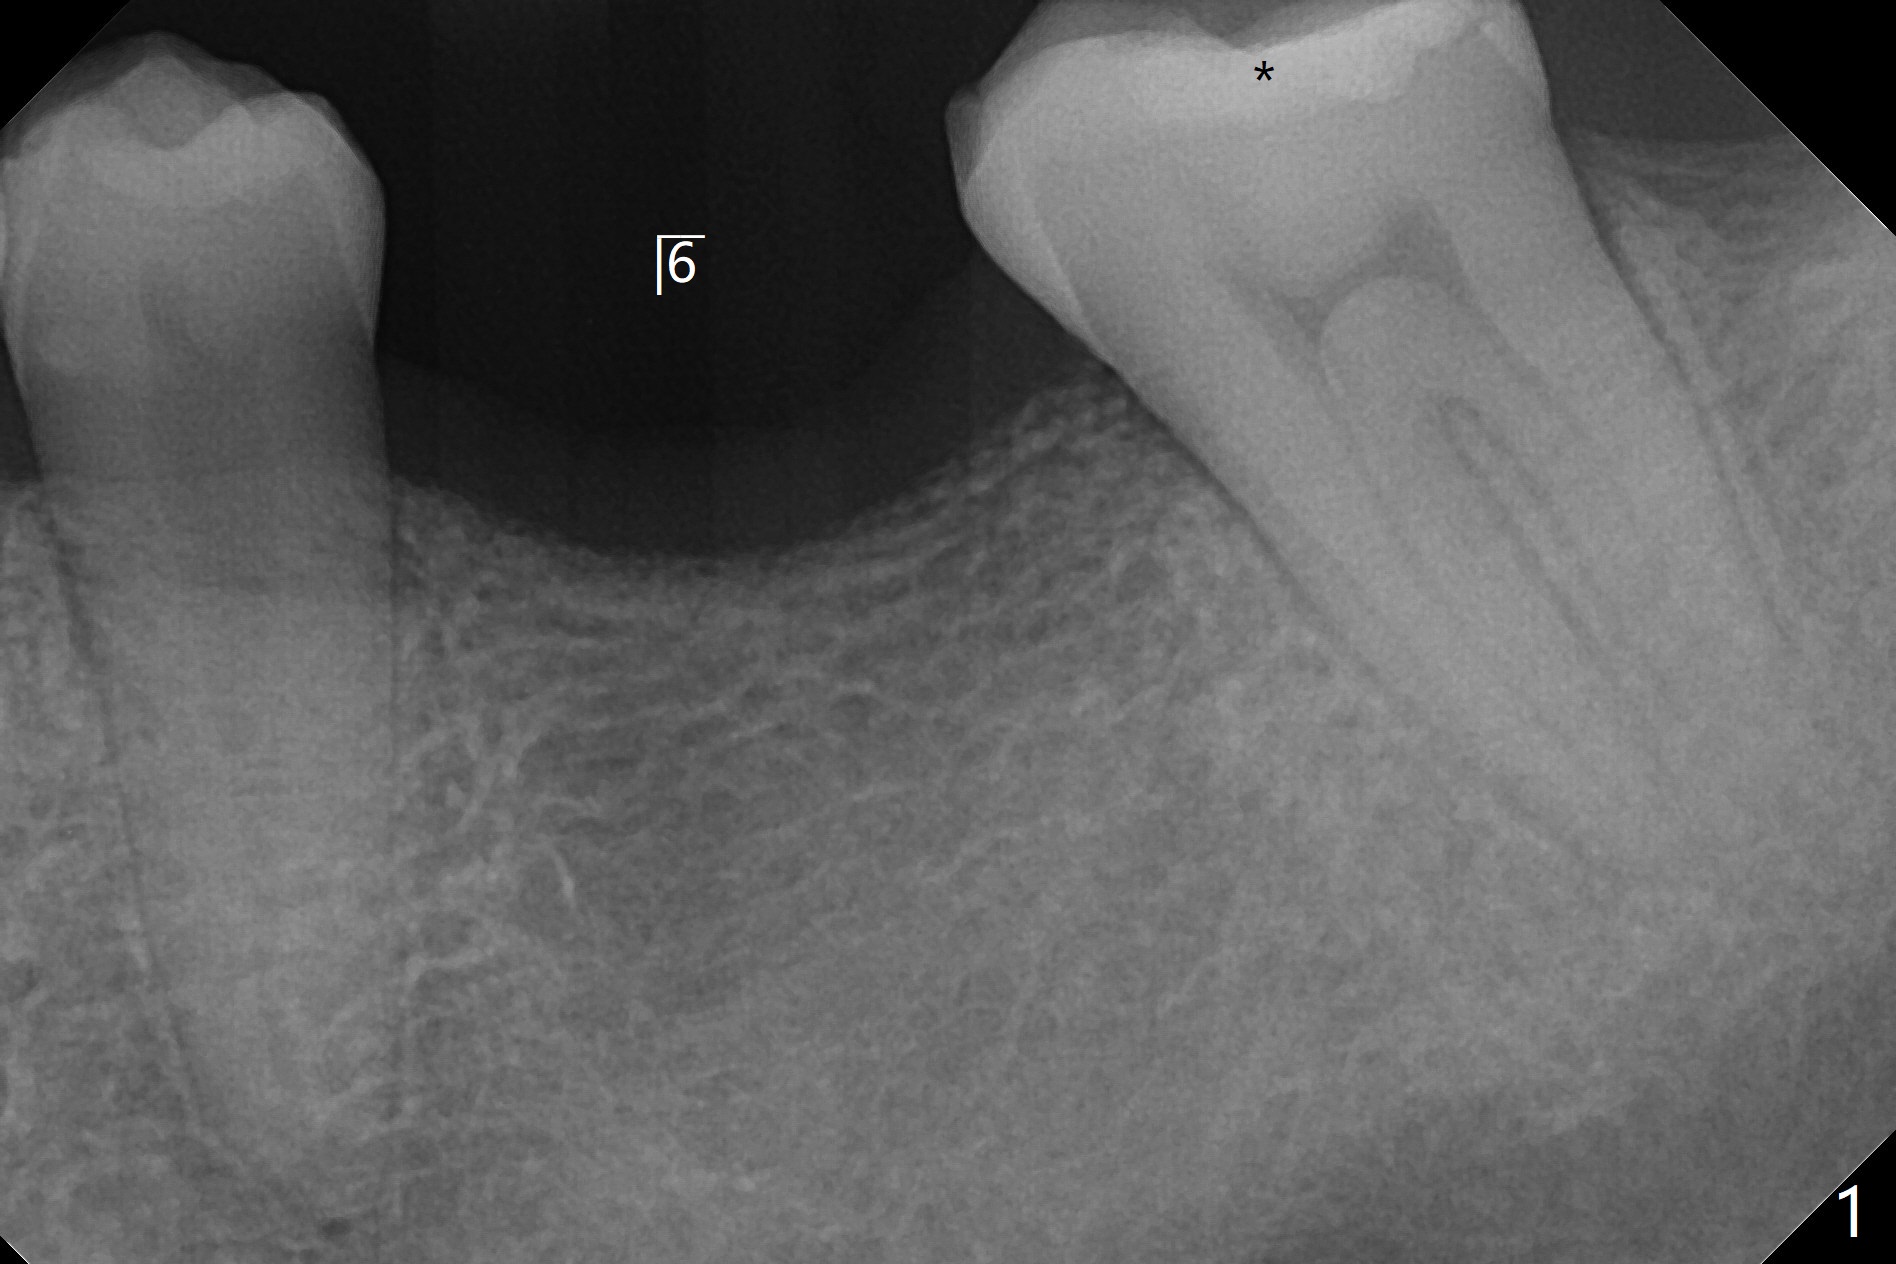

50岁男缺失3个磨牙(包括左下6,图一),左下7严重磨损,树脂修复三次(*),终于同意先做左下种植(图二),骨质宽,但是密度低,可能需要小号钻头,愈合时间多些